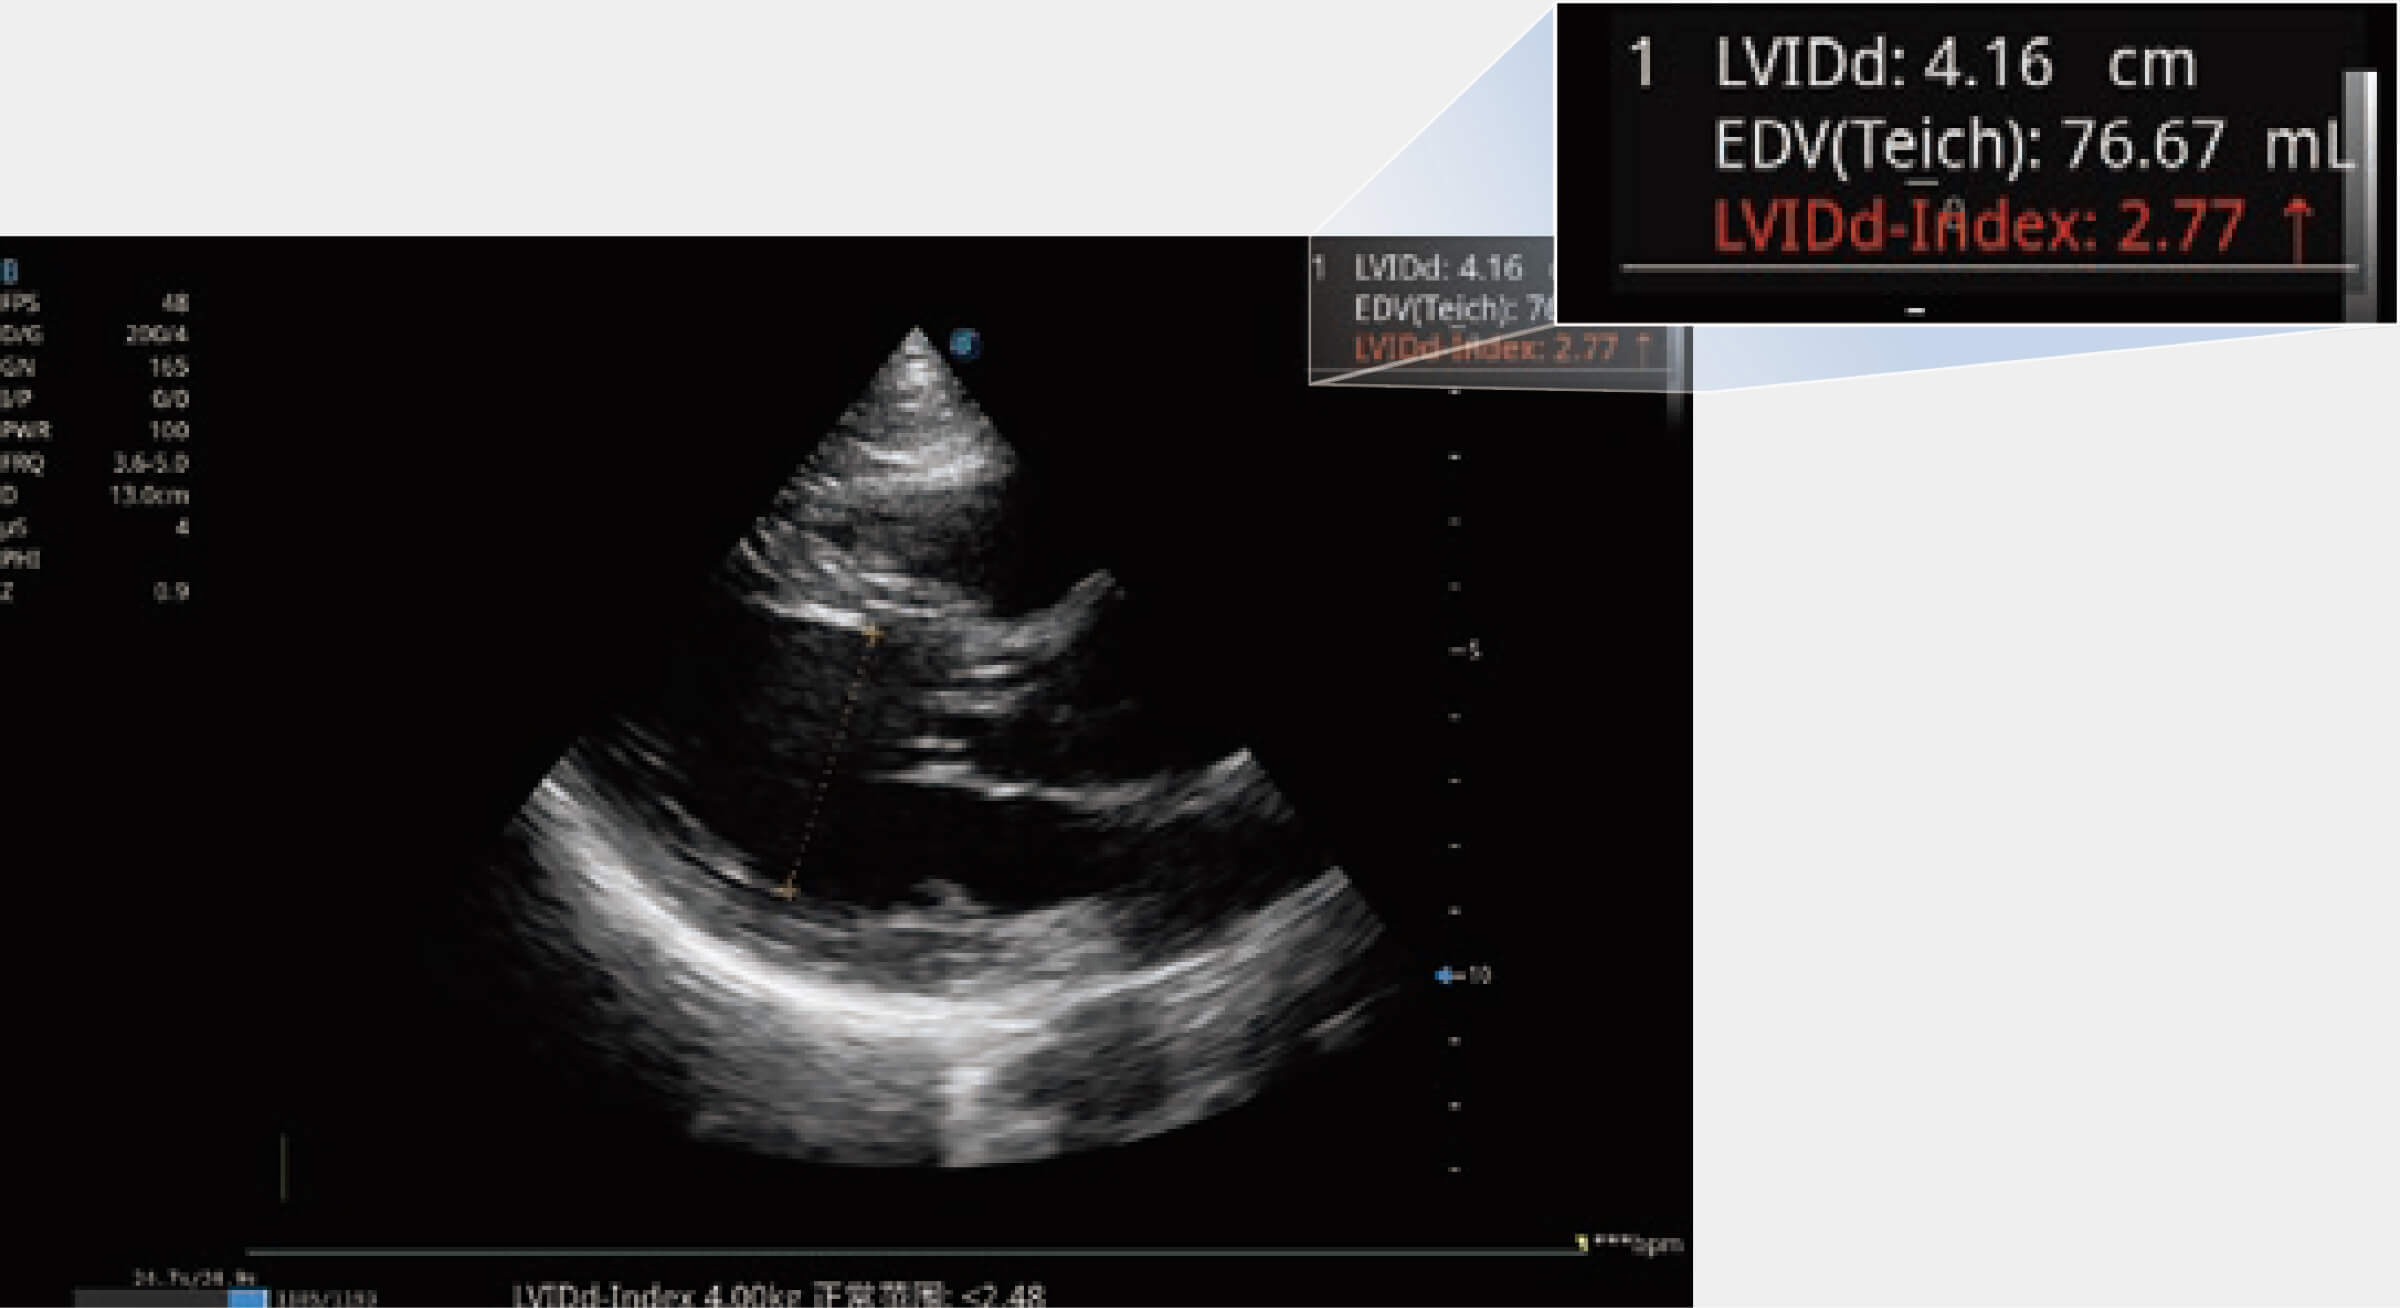

當心臟測量結(jié)果超出正常范圍時,可實時預警提示動物醫(yī)生,減少疾病漏診概率。